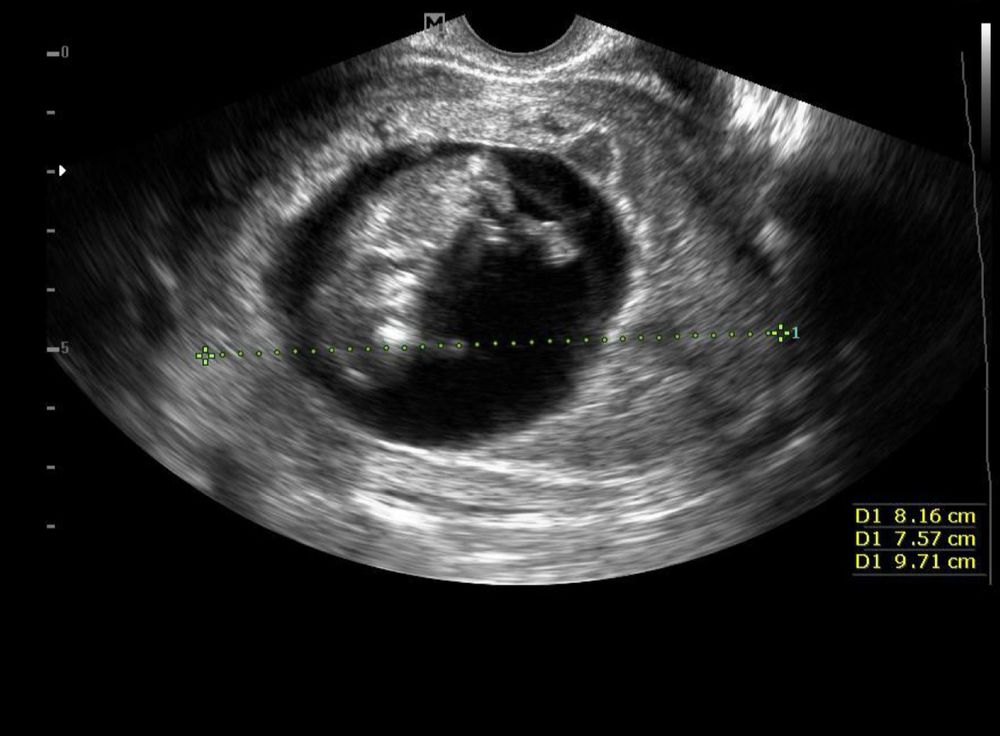

Пол ребенка Узи в 16.5 мальчик или девочка ?